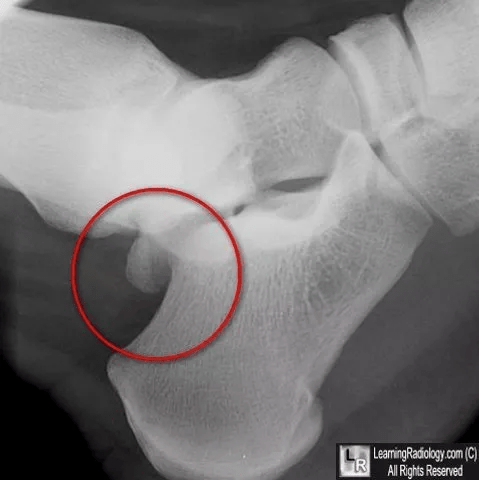

图24:足部前后(a)和斜(b)射线照片.31岁女性,腓侧籽骨纵向骨折.